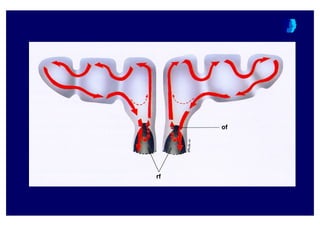

ParanazalParanazal SinSinüüss FizyolojisiFizyolojisi

Bifazik mBifazik muukkuuss öörtrtüüssüü

ÜÜst kat:st kat: KalKal n ve viskn ve visköözz ;; JELJEL

Alt kat:Alt kat: Silialar ile temastaSilialar ile temasta ;; SOLSOL

•• SaSa44ll klkl sinsinüüss sterildirsterildir (<1000 bakteri/gram(<1000 bakteri/gram))

•• MMukozalukozal direndirençç faktfaktöörlerirleri:: Muramidaz,IgA, IgG, IgMMuramidaz,IgA, IgG, IgM

•• MMukusukus öörtrtüüssüü sinsinüüss

ostiumunaostiumuna dodo44ruru

harekethareket edereder

•• SinSinüüss iiççii 1010 dakikadadakikada

tamtam olarakolarak temitemizlenirzlenir